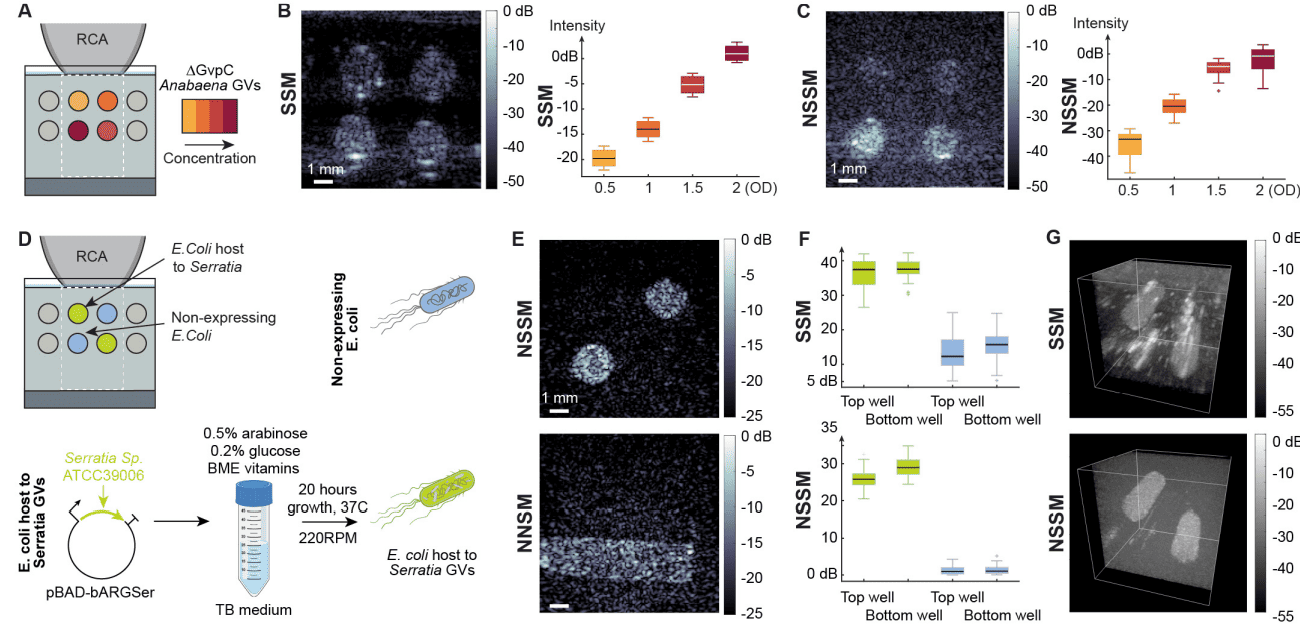

Нелинейная ультразвуковая визуализация является ключом к обнаружению GV в контексте ткани с высокой специфичностью. Чтобы проверить способность NSSM визуализировать генетическую экспрессию в 3D, ученые сначала визуализировали GV, адаптированные как нелинейные бактериальные ARG (изображение №2). GV Anabaena flos aquae очистили и внедрили их в акустически прозрачные фантомы в концентрациях в диапазоне оптических плотностей (OD от optical density) при 500 нм от 0.5 до 2, тем самым имитируя повышение уровней экспрессии в клетках (2A). Фантом был отсканирован с помощью ортогональной последовательности NSSM с использованием шага сканирования 55 мкм. SSM обнаружила скважины GV при всех концентрациях (2B) и нормализованные отношения контрастности к шуму (CNR от contrast-to-noise ratio), масштабированные с шагом 6.9 дБ в среднем от -20.8 дБ для OD 0.5 до 0 дБ для OD 2. NSSM также обнаружила скважины GV при всех концентрациях (2C) и продемонстрировала больший динамический диапазон в 33 дБ между скважиной GV при OD 0.5 и скважиной GV при OD 2. Наблюдалось меньшее увеличение CNR от OD 1.5 до OD 2, что может быть связано с затуханием ультразвука, зависящим от давления, в среде, содержащей изгибающиеся GV.

Далее ученые проверили способность NSSM визуализировать экспрессию бактериального ARG, что представляет особый интерес для области инженерных бактериальных биосенсоров и терапевтических средств. Были использованы два разных штамма E. coli, контрольный штамм и штамм, трансфицированный плазмидой pBAD-bARGSer, что приводит к внутриклеточной продукции Serratia GV, которые конститутивно производят нелинейное рассеяние (2D). Оба штамма бактерий были помещены в агаровые фантомы и визуализированы с помощью NSSM (2E). Объемы визуализации 8.8 x 8.8 x 10 мм3 были реконструированы из 108 положений сканирования звуковых листов RCA-преобразователя (2G). Как и ожидалось, контрольный штамм не показал никакого нелинейного контраста, тогда как бактерии, экспрессирующие Serratia GV, были обнаружены как в 2D, так и в 3D (2E–2G). NSSM обнаружил нелинейные бактериальные ARG с CNR 27 дБ.